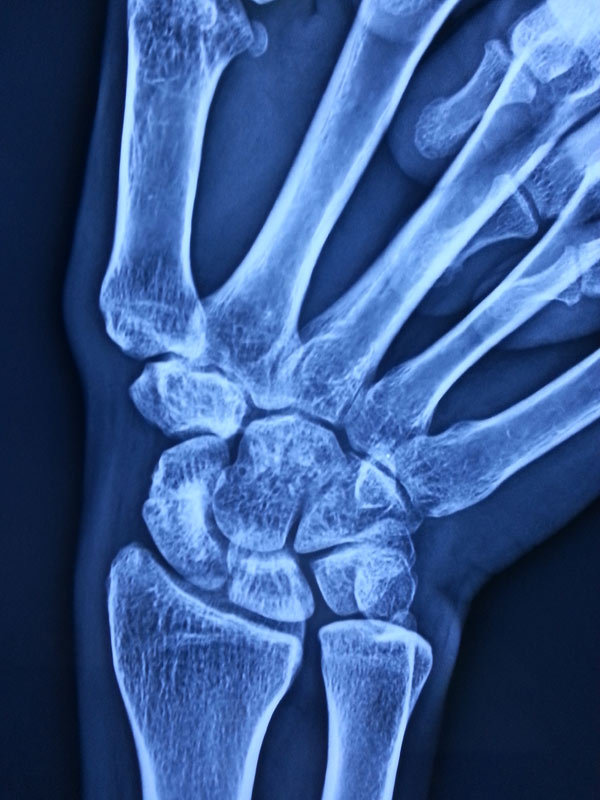

A case of scaphoid non-union

The young, male patient had the fracture of Rt scaphoid/ due to falling on an outstretched hand. The scaphoid fracture was treated, with the plaster cast for 1 ½ month elsewhere. Fracture of Rt Scaphoid was not united. This condition is called, the scaphoid non-union. It was treated with open reduction, and the iliac crest, bone grafting, and K wire stabilization.

3 months post surgery, patients Scaphoid was totally united and he is able to do all activities with his Rt Hand.